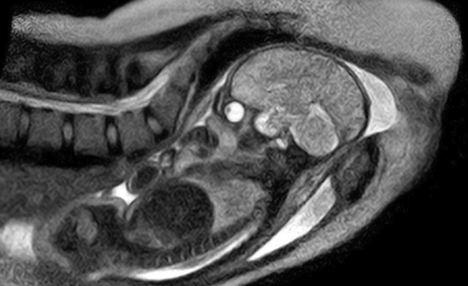

베를린대 부속 자선병원(Charite hospital)의 산부인과 전문의인 에르스트 베인더는 자궁속에서 움직이는 태아의 모습을 MRI(자기공명영상)로 촬영하고 이를 공개했다.

베인더 박사는 출산을 앞둔 산모 여러 명에게 자원 촬영을 권했고 이중 출산이 임박한 산모에게 동의를 구한 뒤 MRI 촬영을 시도했다.

이번 실험에서는 특별한 촬영을 위해 둥근 원통형의 MRI촬영기기 대신 특별하게 ‘뚜껑이 없는’ 오픈형 MRI 기기가 사용됐다.

산모에게 미치는 미세한 충격도 피하기 위해 귀마개를 착용하게 했고, 태아가 자리잡은 복부에는 얇은 막을 씌워 태아가 전자파를 듣고 놀라지 않도록 조치했다.

베이더 박사는 “이전에는 이론으로만 접했던 많은 정보들을 이번 사진을 통해 자세히 알게 됐다.”면서 “이 이미지는 세상의 모든 탄생이 매우 기적적이라는 것을 다시한번 증명한다.”고 덧붙였다.

이어 탄생 직전 태아의 MRI촬영을 통해 태어나기 전 앓을 수 있는 질병 또는 합병증의 진행 과정을 알 수 있고, 산모의 선택에 따라 더욱 안전하고 시기 적절한 제왕절개 시술을 유도할 수 있을 것이라고 기대했다.